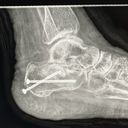

she's been working hard all her life but unfortunately a year and a half she had this unfortunately accident that she broke her heel bone in pieces she was ready to buy her dream house right before this accident happened now she spent all her savings in this situation and now she needs another surgery because the screws are coming out and she can potentially get the bone infected and high risk to get her foot amputate . . she cannot get social security and not disability because she worked with 1099 .. she needs help to keep up with rent and bills and she's terrified to get evicted most because she have two puppies that she needs to protect , and Plus she's been dealing with depression , she's in a good attitude and hope , from my heart thank you. Alma